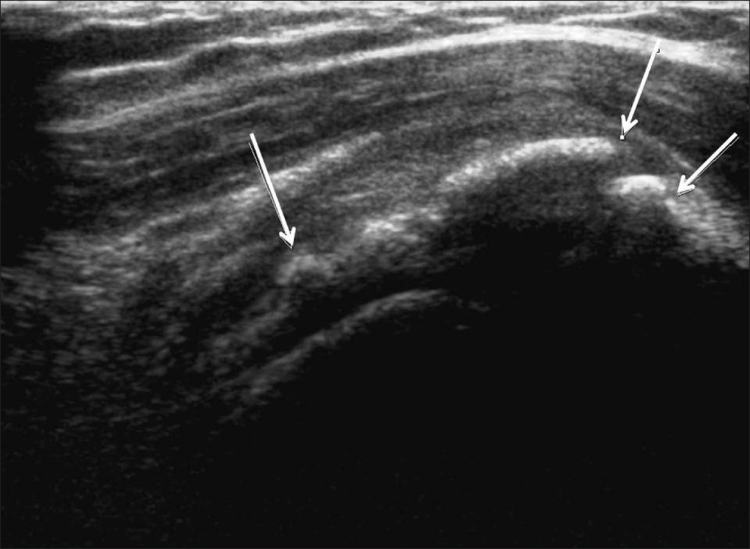

Los desgarros del manguito de los rotadores son la patología más común que se encuentra en los exámenes de ultrasonido del hombro.[7] La incidencia de lágrimas aumenta con la edad. Los desgarros de tendones se pueden clasificar de acuerdo con el grado de falla de la fibra, que van desde desgarros completos [Figura 7], desgarros de espesor total [Figuras 8, 9], desgarros de espesor parcial [Figuras 10-12] y desgarros intrasustancia [Figura 13 ]. Un desgarro agudo suele ir acompañado de derrame articular o bursal [Figura 12]. [7-9] La ausencia de derrame generalmente se relaciona con desgarros crónicos.[9] En un metanálisis sobre la precisión de la resonancia magnética, la artrografía por resonancia magnética y la ecografía en el diagnóstico de desgarros del manguito de los rotadores, la ecografía ofreció una alta sensibilidad y especificidad para la evaluación de los desgarros del manguito de los rotadores de espesor total (92,3 y 94,4 %, respectivamente) con 85,1 % y 92 %, respectivamente para todas las lágrimas.[7] El desgarro de espesor parcial aparece como un defecto o hendidura hipoecogénica en el tendón, afectando solo una parte de su espesor, mientras que un desgarro de espesor total se extiende desde la bolsa hasta la superficie articular del tendón. Un desgarro completo es un desgarro de espesor completo que afecta todo el ancho del tendón. El tendón se retrae medialmente, y la cantidad de retracción depende de la edad del desgarro. En las roturas crónicas, el tendón desaparece por debajo del arco coracoacromial, dejando la cabeza humeral descubierta por el supraespinoso, el denominado signo de la "cabeza desnuda". Los hallazgos de la ecografía incluyen la falta de visualización del tendón y la hernia del músculo deltoides. Los desgarros intrasustancia permanecen localizados en el tendón sin afectar sus márgenes. Los desgarros intrasustancia y de espesor parcial pueden ser difíciles de diferenciar de la tendinopatía focal.